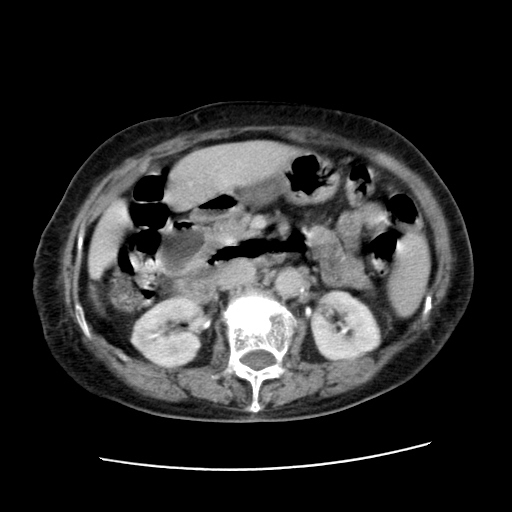

标题: CT25203:上腹部增强,看看

女,77.无不适

肝脏变异、异位胆囊,肝右叶肝内胆管结石并肝内胆管扩张。

肝右叶肝内胆管结石并肝内胆管扩张。

肝右叶肝内胆管结石并肝内胆管扩张

胆总管扩张

肝右叶肝内胆管结石并肝内胆管扩张。胆总管下段梗阻,考虑壶腹部占位。

右侧肝内胆管局限性扩张,其内密度不均匀,扩张的胆管壁增厚,考虑肝内胆管炎合并结石可能性大

肝右叶肝内胆管结石并肝内胆管扩张。胆总管下段梗阻,考虑壶腹部占位。支持